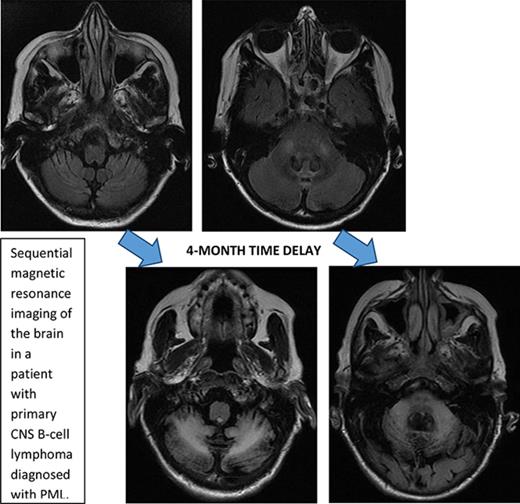

Presentation and imaging findings

Initial symptoms included limb weakness (5 patients), visual loss (3 patients), cognitive impairment/behavior change (4 patients), and a cerebellar syndrome (4 patients). Magnetic resonance imaging abnormalities were restricted to the cerebrum in 12 patients; 2 patients had abnormalities restricted to the cerebellum and brainstem (Figure 1), and 2 patients had abnormalities in both the cerebrum and the brainstem and cerebellum.

Figure 1.

Serial imaging of a patient diagnosed with CLL. Cancer-directed therapy included >6 months of rituximab and idelalisib. (A) Initial magnetic resonance imaging performed 2 months after the onset of headaches and balance disturbance (gait instability and repeated falls) depicting the asymmetric atrophy of the left cerebellum, which was not present in imaging performed 7 months earlier (not depicted). Fluid-attenuated inversion recovery (FLAIR) signal abnormalities are not present elsewhere. (B) Imaging repeated 3 months later (1 month prior to death) showing the continued atrophy of the left cerebellum with new confluent areas of FLAIR signal throughout the left cerebellum and left cerebellar peduncle without enhancement. Again, no FLAIR signal abnormalities are seen in the cerebrum.